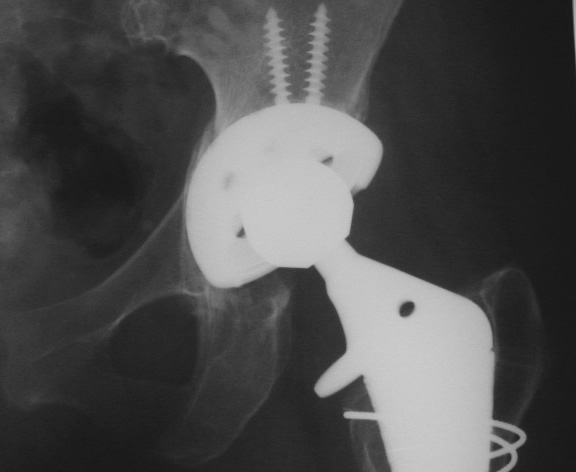

MEDIAL ACETABULAR FRACTURE

Control perforation lateral femoral cortex, reduced by cerclage cables. A control perforation of the lateral femoral cortex was performed in this revision total hip replacement to facilitate removal of the old femoral prosthesis. It is reduced by cerclage cables.